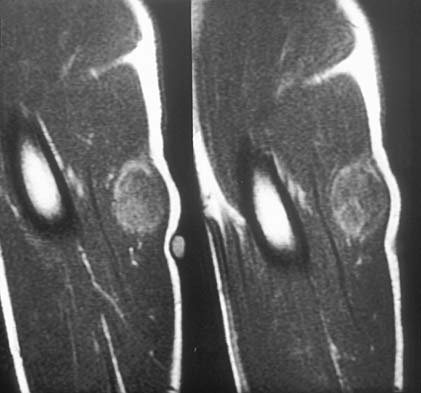

Rhabdomyosarcoma - Pathology - Orthobullets

www.orthobullets.com

www.orthobullets.com

rhabdomyosarcoma orthobullets mri pathology 51a donnell patrick topic

Rhabdomyosarcoma, MRI - Stock Image - C030/6339 - Science Photo Library

www.sciencephoto.com

www.sciencephoto.com

rhabdomyosarcoma mri

MRI Of Rhabdomyosarcoma And Other Soft-Tissue Sarcomas In Children

pubs.rsna.org

pubs.rsna.org

rhabdomyosarcoma mri axial sarcomas rg enhancement